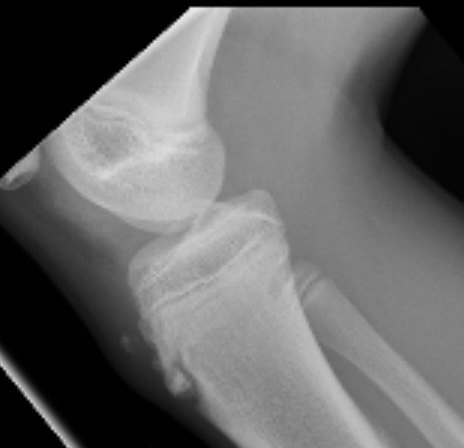

In a month I’ll start to drop updates but I want your thoughts. I also took photos of my growth plates.